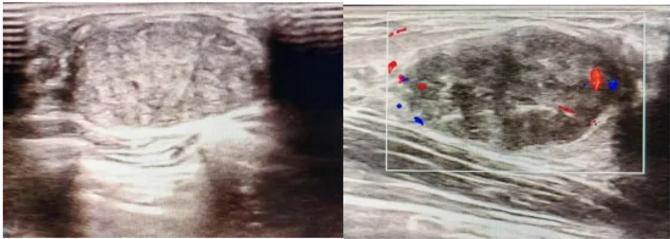

典型表現(xiàn):

橢圓形低回聲團(tuán)塊,包膜完整,內(nèi)部回聲均勻,后方回聲增強(qiáng),周邊無“蟹足樣”浸潤。

血流信號:纖維瘤血流較少,惡性常伴豐富雜亂血流。

形態(tài):良性多呈橢圓形或分葉狀,邊界光滑。

縱橫比: 良性通常<1(橫徑>縱徑) 。

鈣化:粗大鈣化多為良性,細(xì)小簇狀鈣化需警惕惡性。